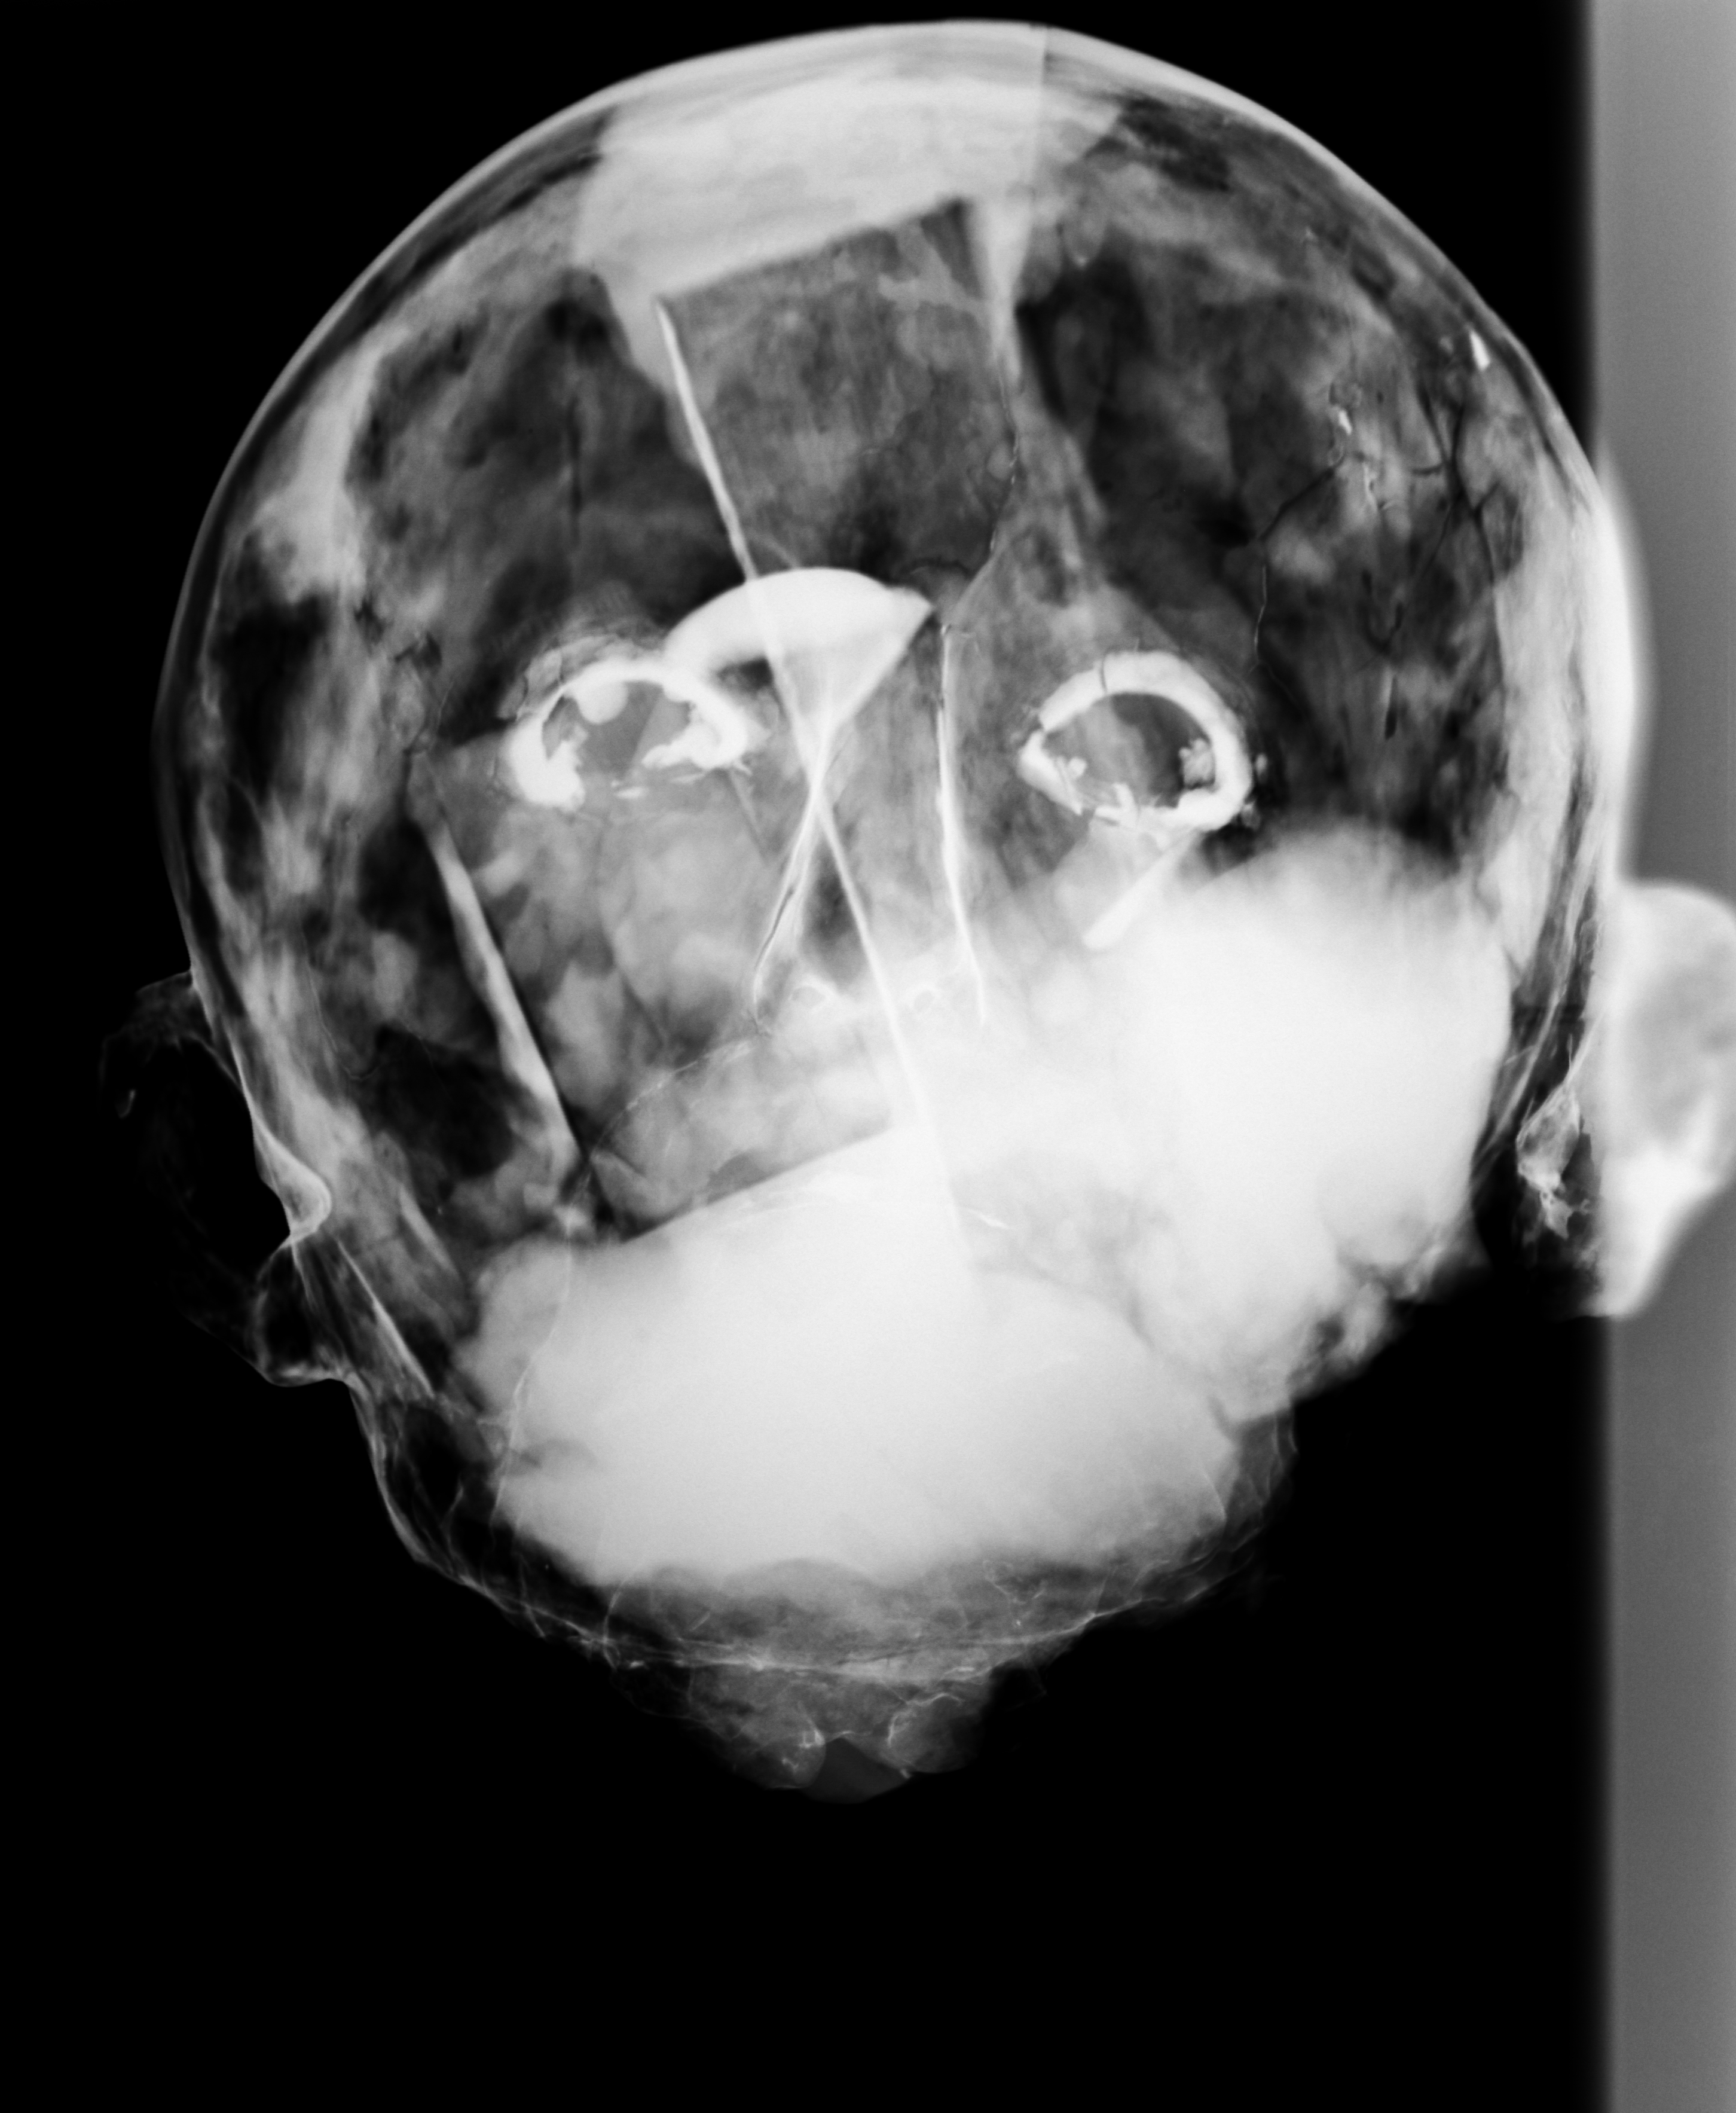

Jesús Nazareno

Siglo XVIII